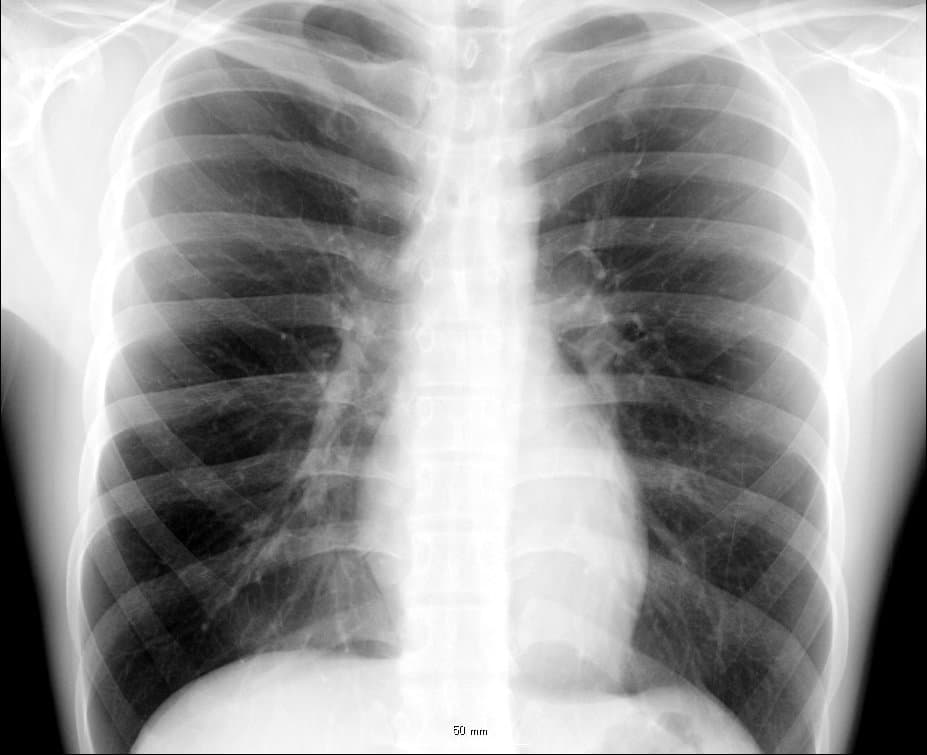

The thorax (: thoraces or thoraxes) or chest is a part of the anatomy of humans, mammals, and other tetrapod animals located between the neck and the abdomen. In insects, crustaceans, and the extinct trilobites, the thorax is one of the three main divisions of the creature's body, each of which is in turn composed of multiple segments. The human thorax includes the thoracic cavity and the thoracic wall. It contains organs including the heart, lungs, and thymus gland, as well as muscles and various other internal structures. Many diseases may affect the chest, and one of the most common symptoms is chest pain. The word thorax comes from the Greek θώραξ thorax "breastplate, cuirass, corslet" via thorax. In humans and other hominids, the thorax is the chest region of the body between the neck and the abdomen, along with its internal organs and other contents. It is mostly protected and supported by the rib cage, spine, and shoulder girdle. Thoracic cavity The contents of the thorax include the heart and lungs (and the thymus gland); the major and minor pectoral muscles, trapezius muscles, and neck muscle; and internal structures such as the diaphragm, the esophagus, the trachea, and a part of the sternum known as the xiphoid process. Arteries and veins are also contained – (aorta, superior vena cava, inferior vena cava and the pulmonary artery); bones (the shoulder socket containing the upper part of the humerus, the scapula, sternum, thoracic portion of the spine, collarbone, and the rib cage and floating ribs). External structures are the skin and nipples. In the human body, the region of the thorax between the neck and diaphragm in the front of the body is called the chest. The corresponding area in an animal can also be referred to as the chest. The shape of the chest does not correspond to that part of the thoracic skeleton that encloses the heart and lungs. All the breadth of the shoulders is due to the shoulder girdle, and contains the axillae and the heads of the humeri.